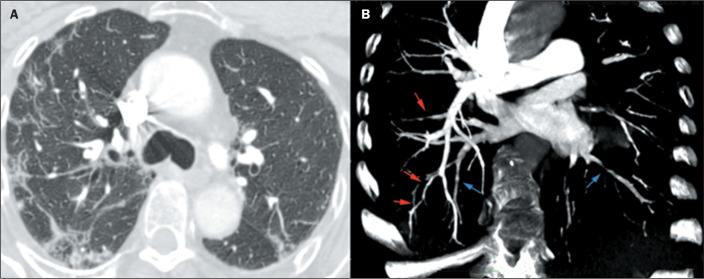

Objective: The purpose of this study was to evaluate the characteristics and meaning of the vessel wall irregularities sign, observed on computed tomography angiography of the pulmonary arteries of patients with coronavirus disease 2019 (COVID-19) pneumonia.

Results: The vessel wall irregularities sign was observed in 50 (76.9%) of the 65 patients with COVID-19. Among those 50 patients, the vascular involvement was predominantly mixed (arterial and venous) in 43 (86%), subsegmental in all 50 (100%), segmental in 13 (26%), bilateral in 46 (92%), affecting 4-5 lobes in 35 (70%), mainly in the right lower lobe in 46 (92%), and mainly in the left lower lobe in 44 (88%).

Conclusion: The vessel wall irregularities is a prevalent sign of vascular involvement in patients with COVID-19.